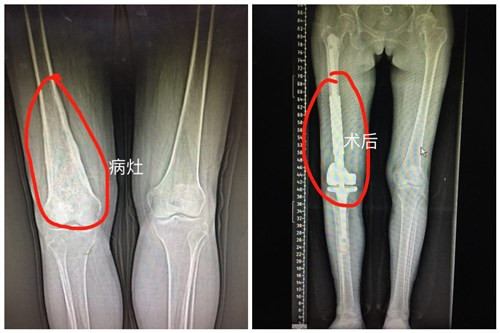

近日,临床医学院/附属医院骨科成功为一“股骨远端恶性肿瘤”患者行右股骨远端软骨肉瘤病灶切除+假体置换术,该手术为九江市首例。目前患者已康复出院。

患者杜女士,53岁,右膝关节反复疼痛一年多。辗转多家医院求医,均建议患者行截肢手术,不甘心的杜女士及家属慕名来临床医学院/附属医院骨科就诊。骨三科朱述浪主任带领的刘剑军等医师团队详细了解患者病情之后,立即召开病情讨论会,病理结果显示该患者所患为“软骨肉瘤”。为避免给患者带来身体及心理上的双重痛苦,改善其心理感受及提高生活质量,朱主任团队决定最大限度保留患者的肢体功能,并为患者制定了精准的手术方案及个性化的人工膝关节肿瘤假体。手术过程顺利,手术时长不到2小时,术中出血仅150ml,术后患者膝关节功能恢复良好,很快能下地活动。出院前患者握着医护人员的手说:“来附属医院求医是最正确的选择,不仅减轻我的病痛,同时让我感觉到你们的耐心、责任心,你们亲切的语言,微笑的脸庞,让病房充满了阳光,充满温馨。你们是最好的医护团队。”